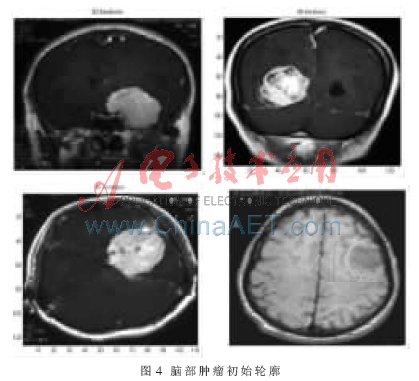

根据初始轮廓模型,应用改进主动轮廓模型提取脑部肿瘤边缘。图4为一组勾画了脑部肿瘤初始轮廓的MR图像,图5为在图4的初始轮廓下,基于改进主动轮廓模型提取的肿瘤边缘。从图5可以看出,基于改进主动轮廓模型提取脑部肿瘤边缘不仅能够接近真实边缘的凹陷处,而且快速收敛到物体的真实边缘。实验结果证明,主动轮廓模型中改进的一阶连续性能量是有效的,使初始轮廓能够接近物体凹部,同时很好地保持了个点之间的连续性,改变了原始主动轮廓模型的非凸性性质。由于增加了自适应改变大小的外部约束力来增大外能的吸引范围,因此主动轮廓模型不依赖初始位置的选取。